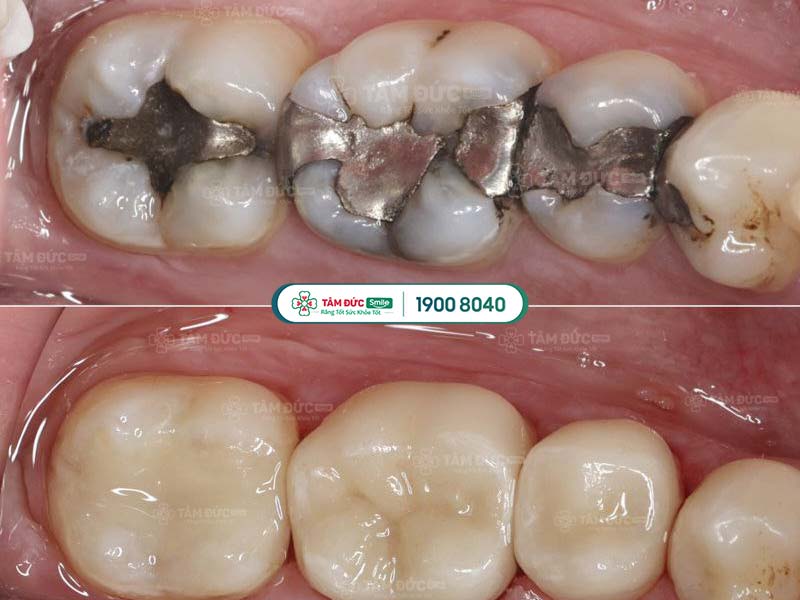

1.4. Thay miếng trám mới

Hiệu quả trám răng không thể duy trì vĩnh viễn. Theo thời gian, miếng trám răng cũ có thể bị bong tróc hoặc rơi ra do tác động từ lực ăn nhai. Trong trường hợp này, bác sĩ sẽ yêu cầu thay miếng trám răng mới.

Quý khách cần trám lại răng khi miếng trám cũ bị bong tróc

2.1. Amalgam

Amalgam (hoặc còn gọi là trám bạc) là vật liệu trám răng có màu bạc, xuất hiện từ lâu trên thị trường nha khoa. Thành phần chủ yếu của Amalgam bao gồm: Bạc, kẽm, đồng, thiếc và thủy ngân.

Loại vật liệu này rất bền, có độ chịu lực tốt và giá thành rẻ nhất trong tất cả các loại vật liệu trám răng. Tuy nhiên, do Amalgam có màu sắc khác biệt với màu răng, nên không được đánh giá cao về thẩm mỹ.

Răng được phục hình sau khi trám